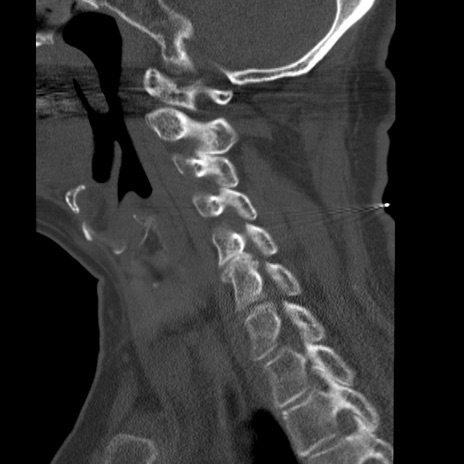

症例50 頚椎CT(矢状断像)

【症例】60歳代女性

【主訴】後頭部〜右後頸部にかけての痛み

【現病歴】本日飲食店でコーヒーを飲んでいたところ、突然後頭部〜右後頸部にかけて痛みが出現し、右上肢の感覚障害を伴ったため救急要請。

【身体所見】脳神経学的に明らかな異常所見を認めず。右上肢に軽度の感覚障害あり。

異常所見と診断は?

頚椎CT